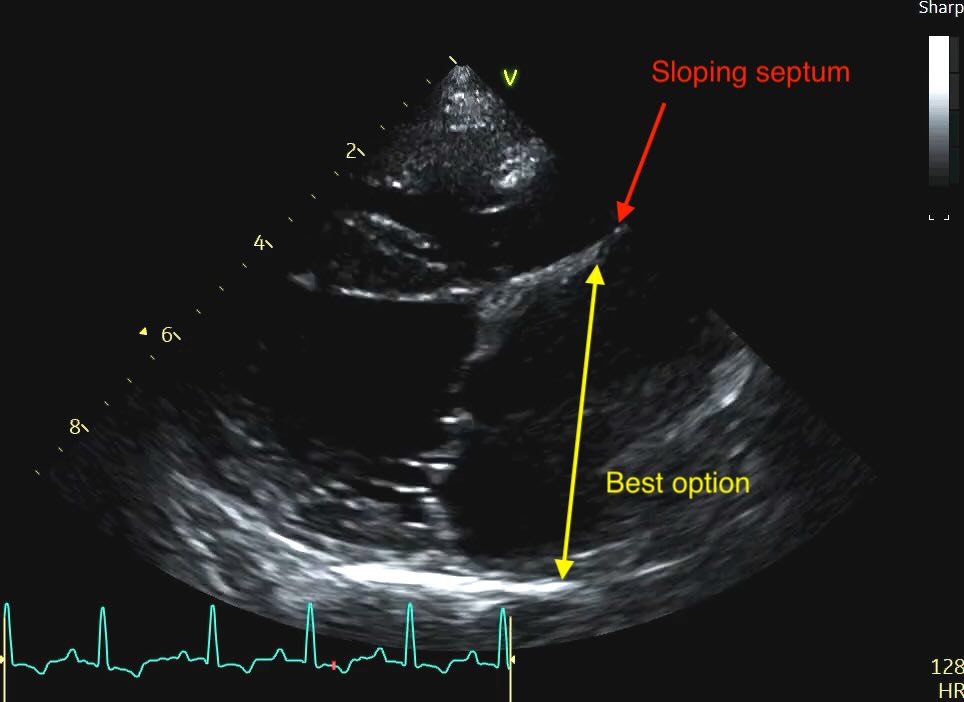

The Problem of the “Bowed” Septum

Sometimes you’ll see a distended or “bowed” interatrial septum, often sloping up to the right on the view merging with some dilated pulmonary veins. In a volume-overloaded heart, the high pressure in the left atrium often causes the septum to bulge significantly into the right atrium.

Clinical Recommendation: When the septum is distended, do not measure from the most “sunken” point. Instead, measure from the middle of the septal curvature to the posterior wall, ensuring your line remains strictly parallel to the mitral annulus. Subjectively, a septum that loses its horizontal orientation and “blows out” into the right heart is a strong red flag for elevated filling pressures, even if your linear measurement is borderline.